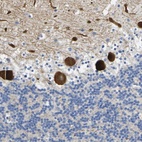

Immunohistochemical staining of human cerebellum shows strong cytoplasmic positivity in Purkinje cells.